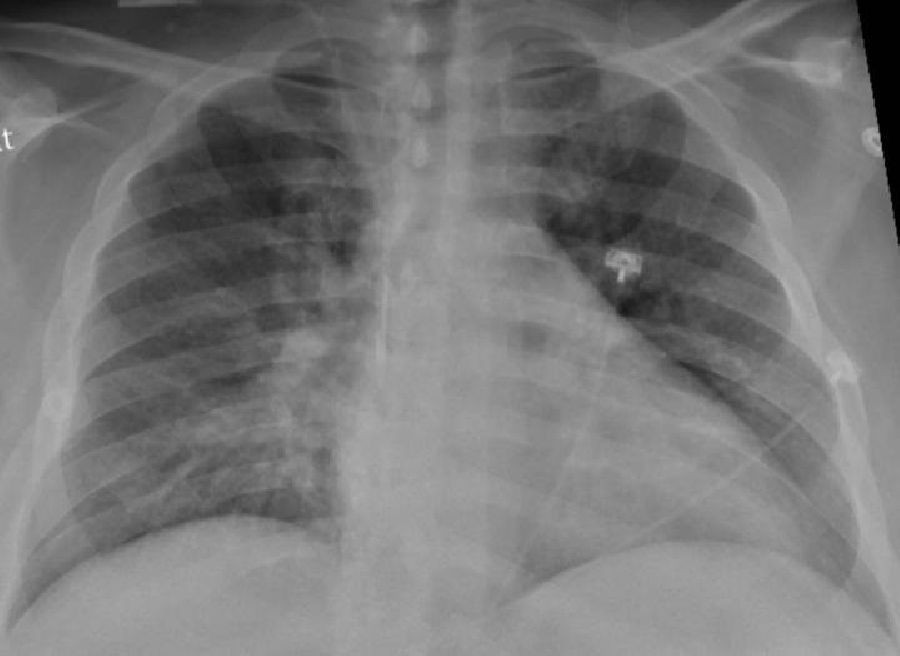

Investigadores de BRN piden "extremar la prevención" contra la neumonía adquirida en la comunidad mediante la vacunación

Los investigadores de la red Barcelona Respiratory Network (BRN) han pedido "extremar la prevención" contra la neumonía adquirida en la comunidad, especialmente entre las personas más vulnerables, a través de vacunas tales como la antigripal o la del Covid-19, que pueden conducir a esta enfermedad, así como la vacuna antineumocócica 20-valente, especialmente para mayores de 65 años, con motivo del Día Mundial de la Neumonía, que se celebra este martes.

La neumonía adquirida en la comunidad tiene una incidencia de entre cuatro y diez casos por cada 1.000 habitantes por año, y su mortalidad en casos hospitalizados en países desarrollados se encuentra entre el 4 y el 14 por ciento, aunque en los casos graves puede llegar al 30 por ciento, según un comunicado de BRN.